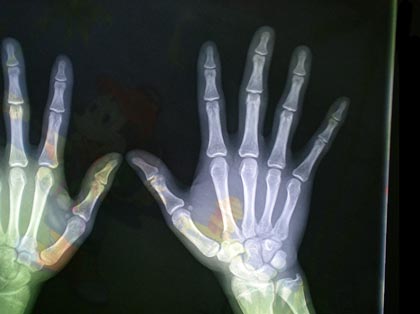

(图:徐阿姨来院时所拍摄的腕关节CT图)

经过问诊和体查,马友文主任初步诊断为风湿性关节炎,全身大关节都受到了或多或少的影响。随后马友文主任给徐阿姨做了辅助检查,并从风湿四项,细胞学检查,微生物学等方面入手检查。经过这些检查,能更清晰有力的判断出徐阿姨确实是风湿性关节炎。